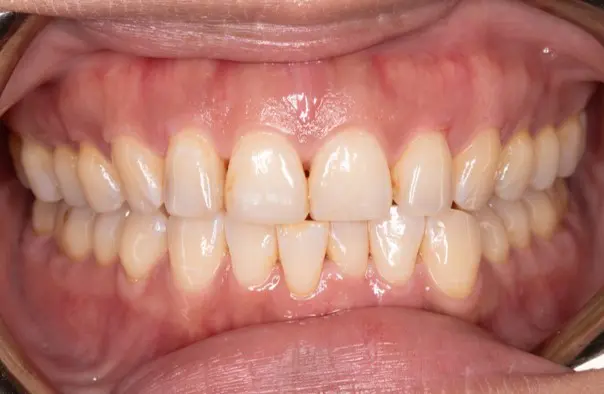

Before

After